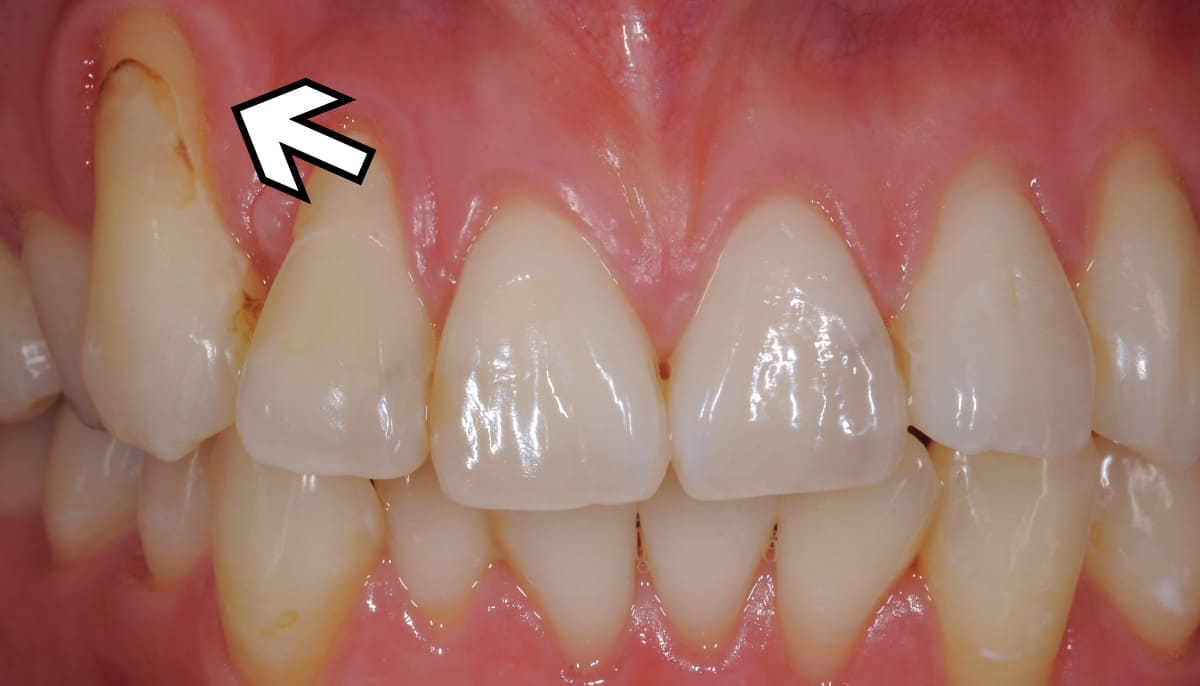

根面被覆|歯の根元の欠損部に自らの歯ぐきを移植。

Before

After

歯ぐきが下がって歯の根元が露出してしまった状態を改善する治療。最も多く行われているのは歯ぐきの移植。上顎の歯ぐきは切除しても再生するのでこの部分を患部に移植する。見た目はもちろん知覚過敏の改善にもつながる。

【料金】15万円〜

【治療期間】3か月〜6か月程度